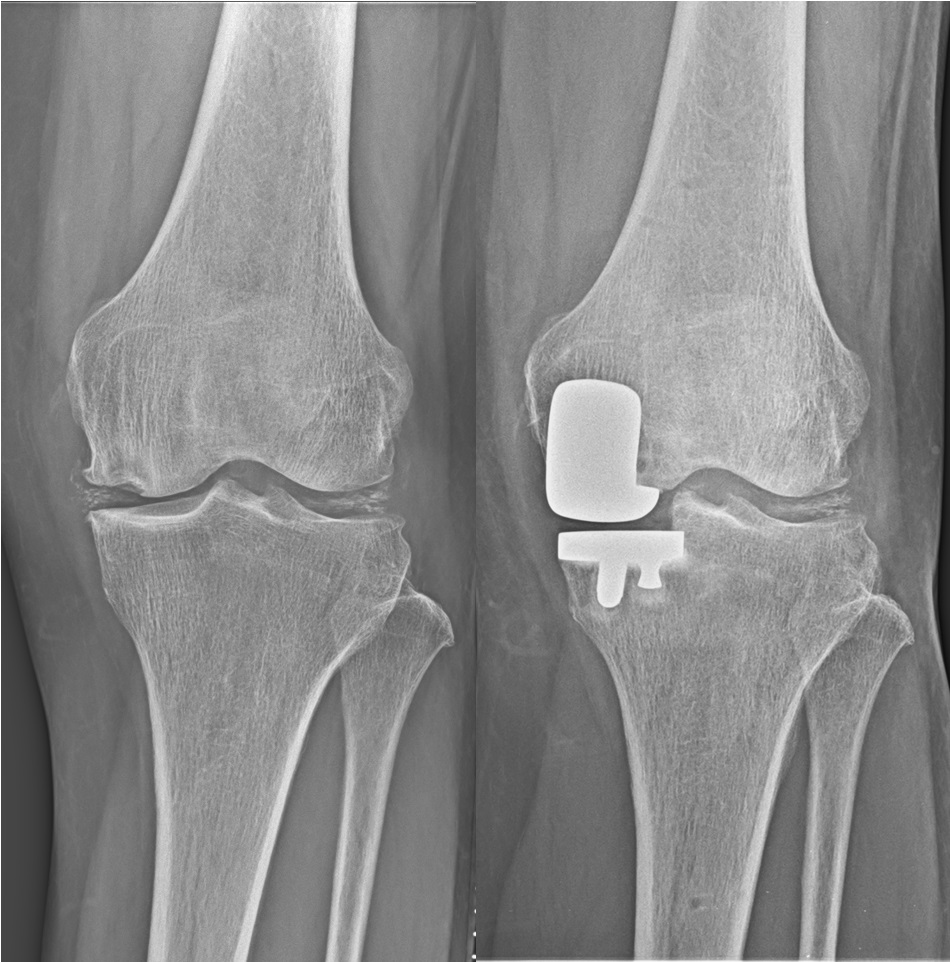

人工膝関節単顆置換術(unicompartmental knee arthroplasty: UKA)

膝関節の内側または外側のみの変形に対して適応があります。

片側のみの人工関節置換術であることから、体への負担が少なく、早期より痛みが改善し歩行が可能となります。